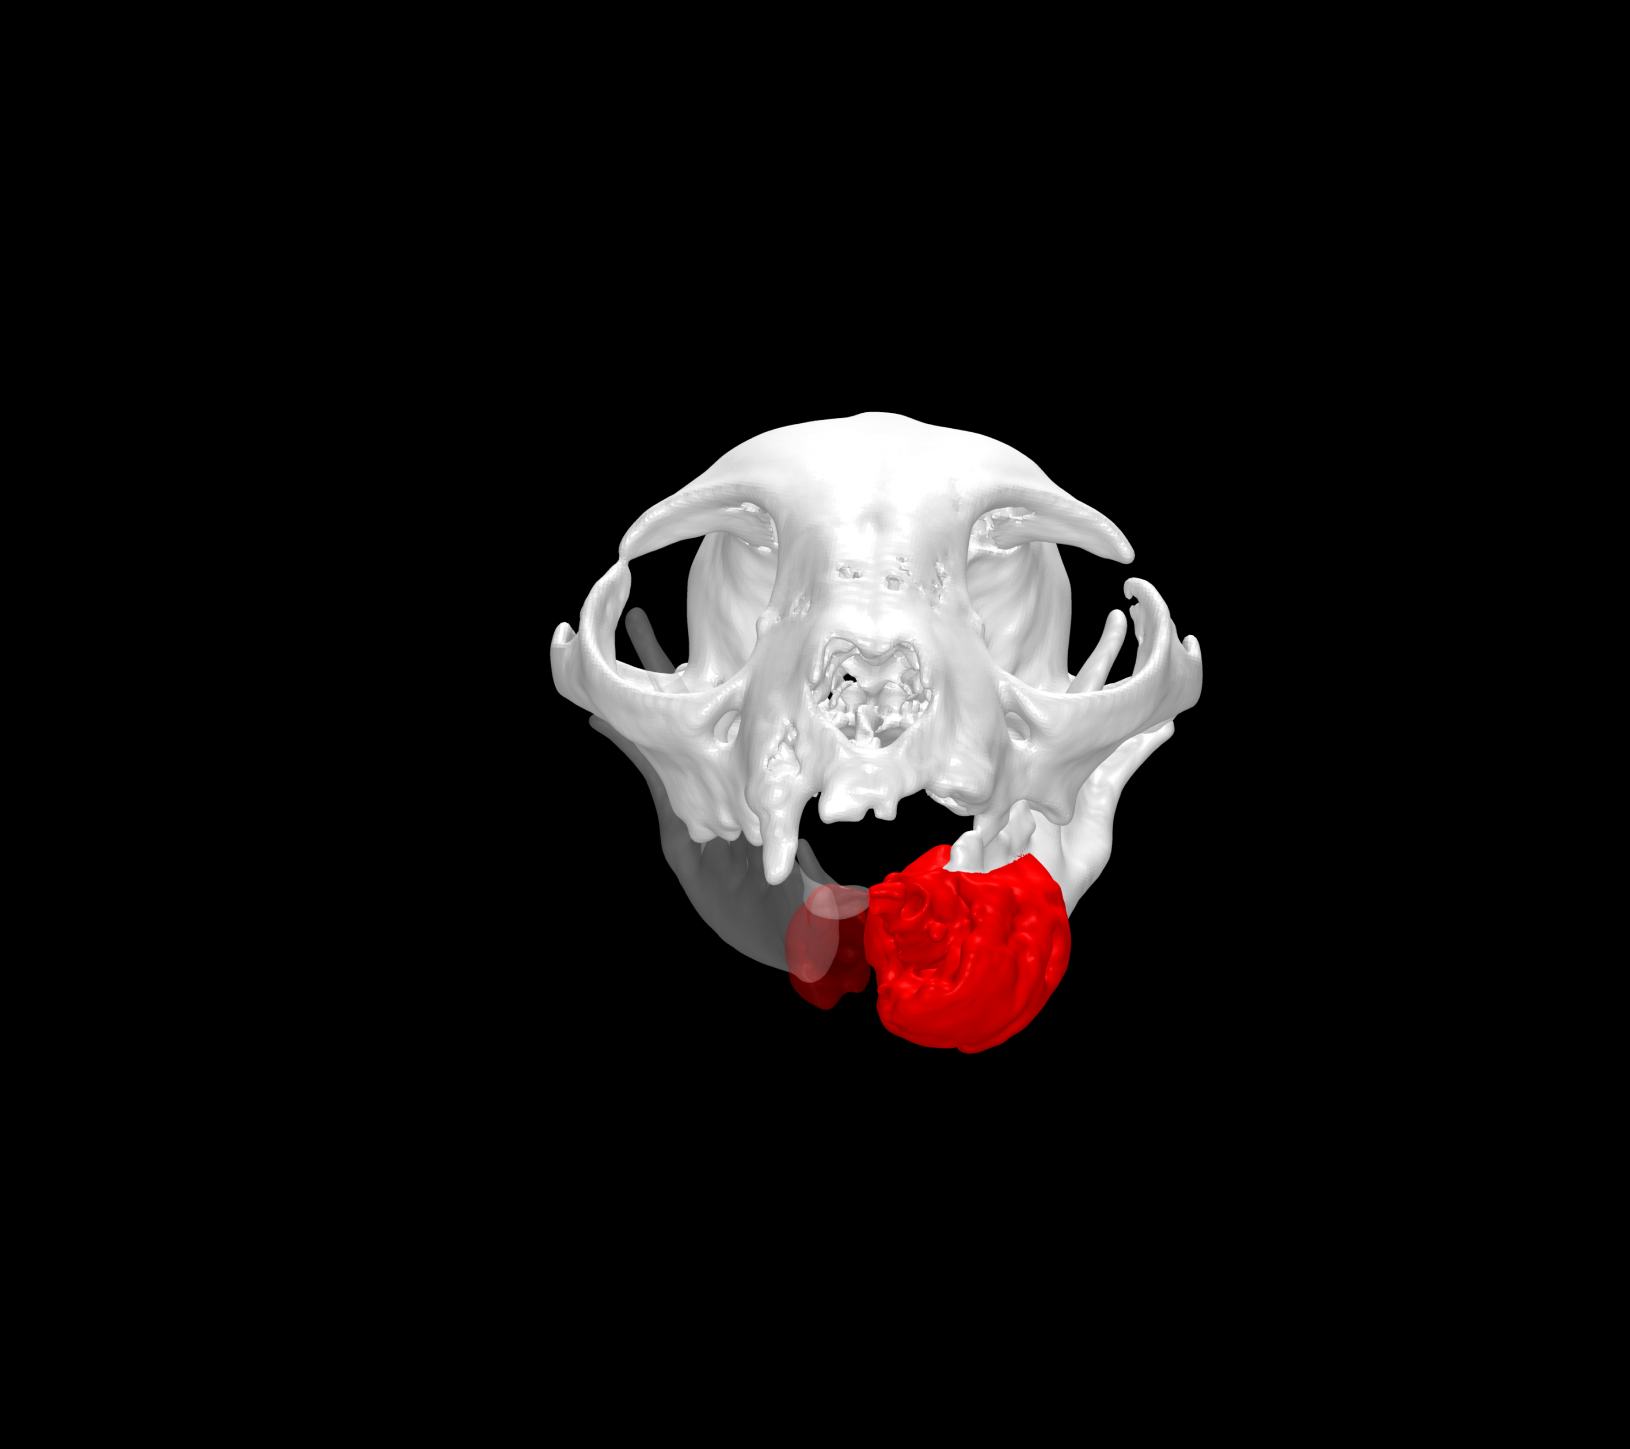

Esto se consigue gracias a los avances en la tecnología de fabricación, como la impresión 3D. Con esta tecnología se pueden crear implantes personalizados tanto en acero quirúrgico como en titanio a partir de imágenes médicas de tomografías computerizadas (TC) o resonancias magnéticas (RM).

- Mejor ajuste y adaptación al paciente: favorece la colocación precisa y la estabilidad del implante sobre la anatomía quirúrgica.